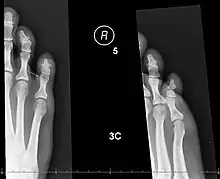

X-rays of fractures of the proximal (left) and distal (right) phalanges in the little toe. | |

The AO Foundation/Orthopaedic Trauma Association (AO/OTA) classification generates numeric codes for describing broken toes.[8] They run 88[meaning a fracture of the phalanges].[number-code of toe, with the big toe=1 and the little toe=5].[number-code of phalanx, counting 1-3 outwards from the foot].[number-code of location on the bone, with 1 being the inner end, 3 the outer, and 2 in-between].[8] So, for instance, 88.1.2.1 means a fracture to the big toe's innermost bone, at the proximal end.[8][9] A letter can be added to describe the fracture pattern.[9]